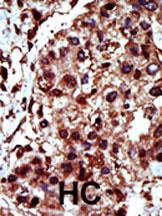

Formalin-fixed and paraffin-embedded human cancer tissue reacted with the primary antibody, which was peroxidase-conjugated to the secondary antibody, followed by AEC staining. This data demonstrates the use of this antibody for immunohistochemistry; clinical relevance has not been evaluated. BC = breast carcinoma; HC = hepatocarcinoma.